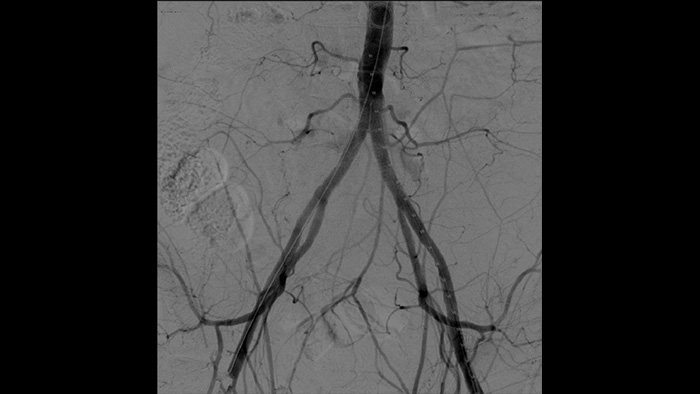

Digital subtraction angiography (DSA) is used in interventional vascular procedures to clearly visualise blood vessels by removing structures that can obscure vessel visibility. Roadmap fluoroscopy overlays a previously acquired subtracted contrast image on the live fluoroscopy, allowing you to track a device without reinjecting contrast.

With the Zenition, our DSA image quality has improved greatly. We no longer see a grainy image. We just see a very clear image."

Dr. R. Vila, MD

Bellvitge University Hospital, Barcelona, Spain